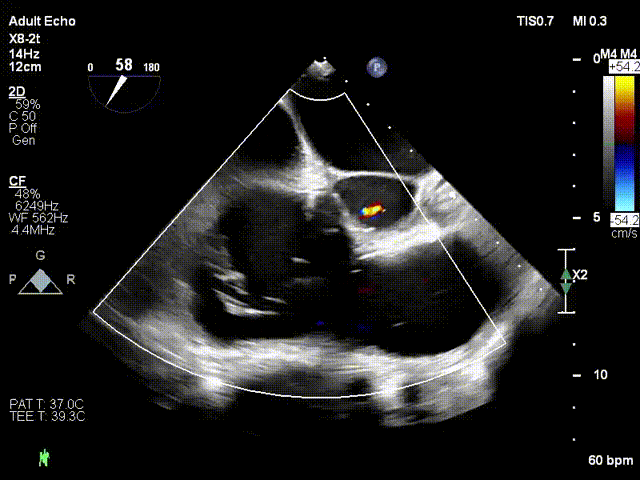

术前超声

术后超声